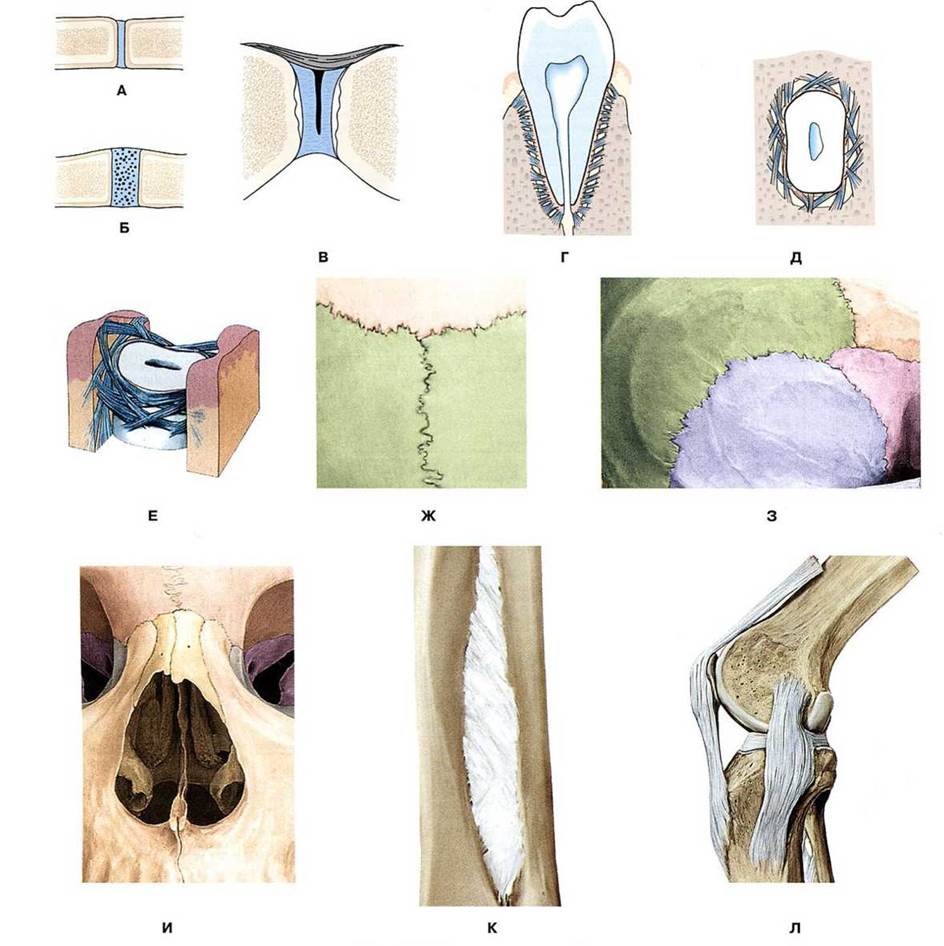

Структура и анатомия синдесмоза: научные иллюстрации